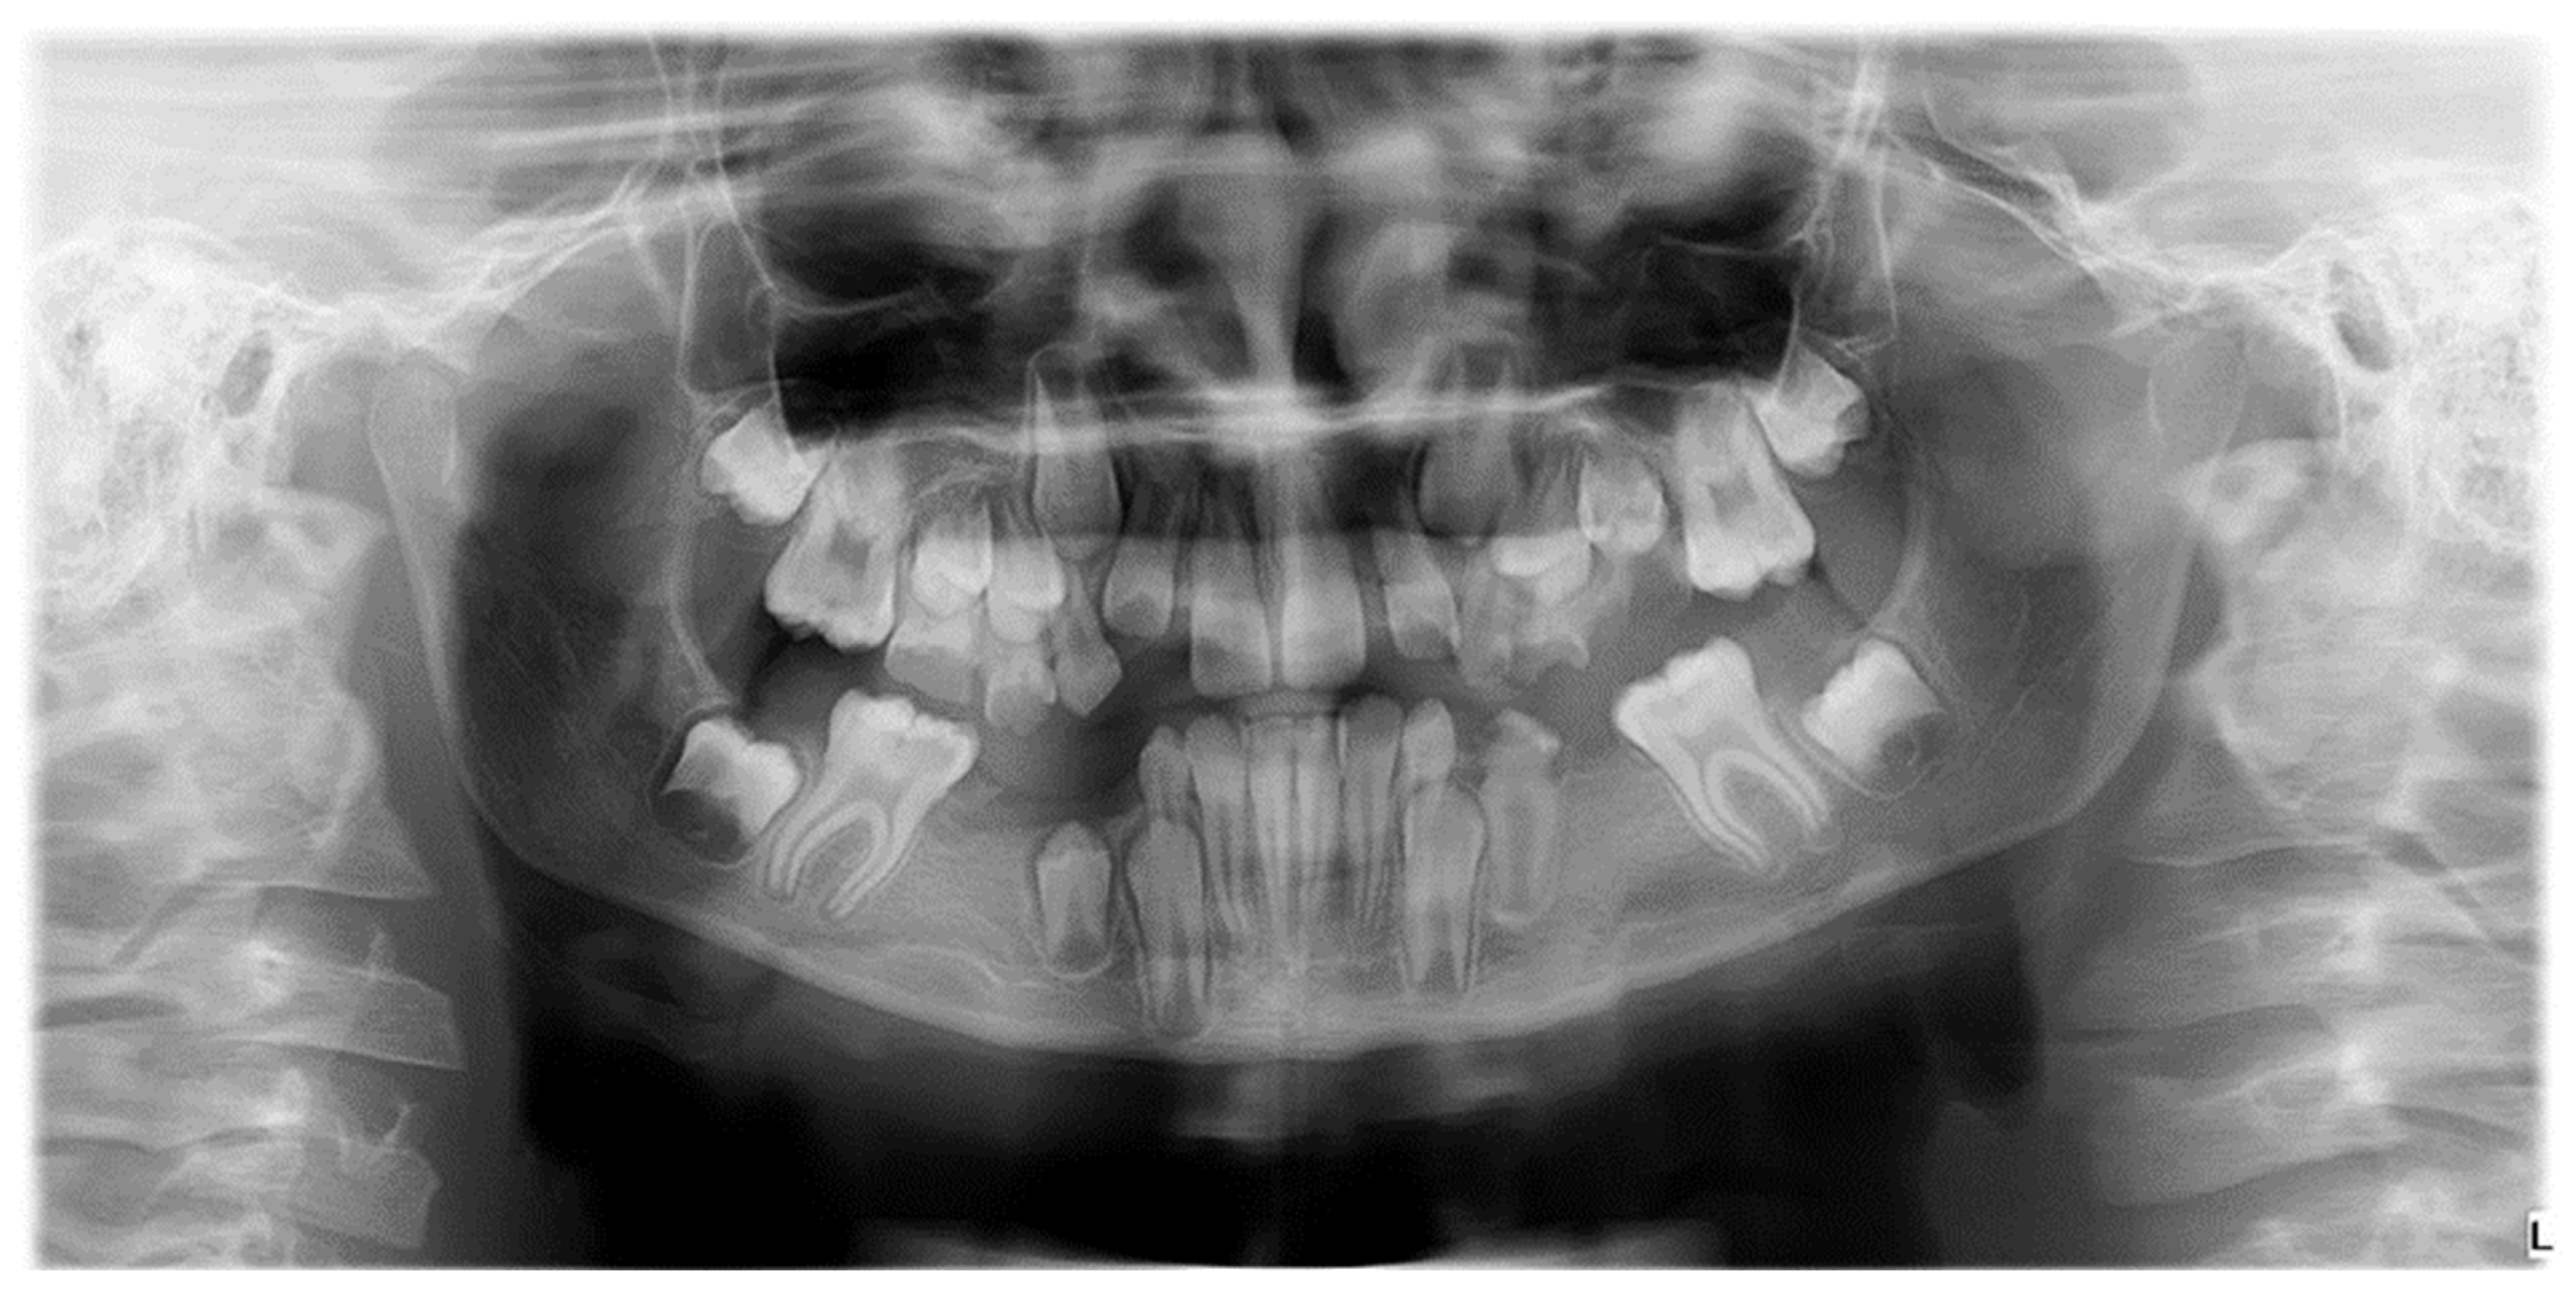

Confirming existing evidence regarding etiological links and exploring new, previously undetected associations is of particular importance, given that, to date, no studies have been conducted in Romania on the etiology of MIH in correlation with other coexisting anomalies to optimize treatment. The high prevalence of dental anomalies, especially hypodontia, in children with MIH is a new and clinically significant finding, requiring further research due to its potential implications for evaluation and treatment planning (Figure 3) [21].

Figure 3.

Radiographic image illustrating hypodontia in a patient with mixed dentition and clinical diagnosis of Molar-Incisor Hypomineralization.